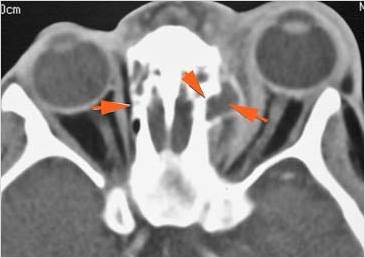

Orbits

The extraconal orbital fat is abnormal.

There is a subperiosteal abscess or edema along the medial wall, roof or floor of the orbit.

The extraocular muscles are swollen or otherwise abnormal.

There is bone erosion along the walls of the orbit.

Eyes

Proptosis is present.

The optic nerve is stretched in appearance.

Signs of tension orbit or endophthalmitis are present.